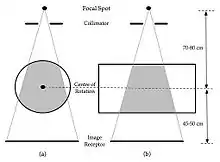

- The imaging geometry for C-Arm CT is illustrated in Figure 7.15. The XRT and image receptor take images from different angles around the patient at a magnification of ~1.5. Partial rotations of 150-200o have been found to be adequate - not the full 360o as in helical CT. In addition, rotations can be in orbital as well as oblique planes. Rotation speeds of 30o per second and imaging frame rates of 7.5-10 frames per second are typically used to acquire 50 or more 2D projections.

- Furthermore, it has been found that the focal spot should be located on a line, perpendicular to the image receptor, which contains the chest wall margin. Equally importantly, the collimator should also be adjusted to ensure that the X-ray beam intercepts the image receptor on that margin.